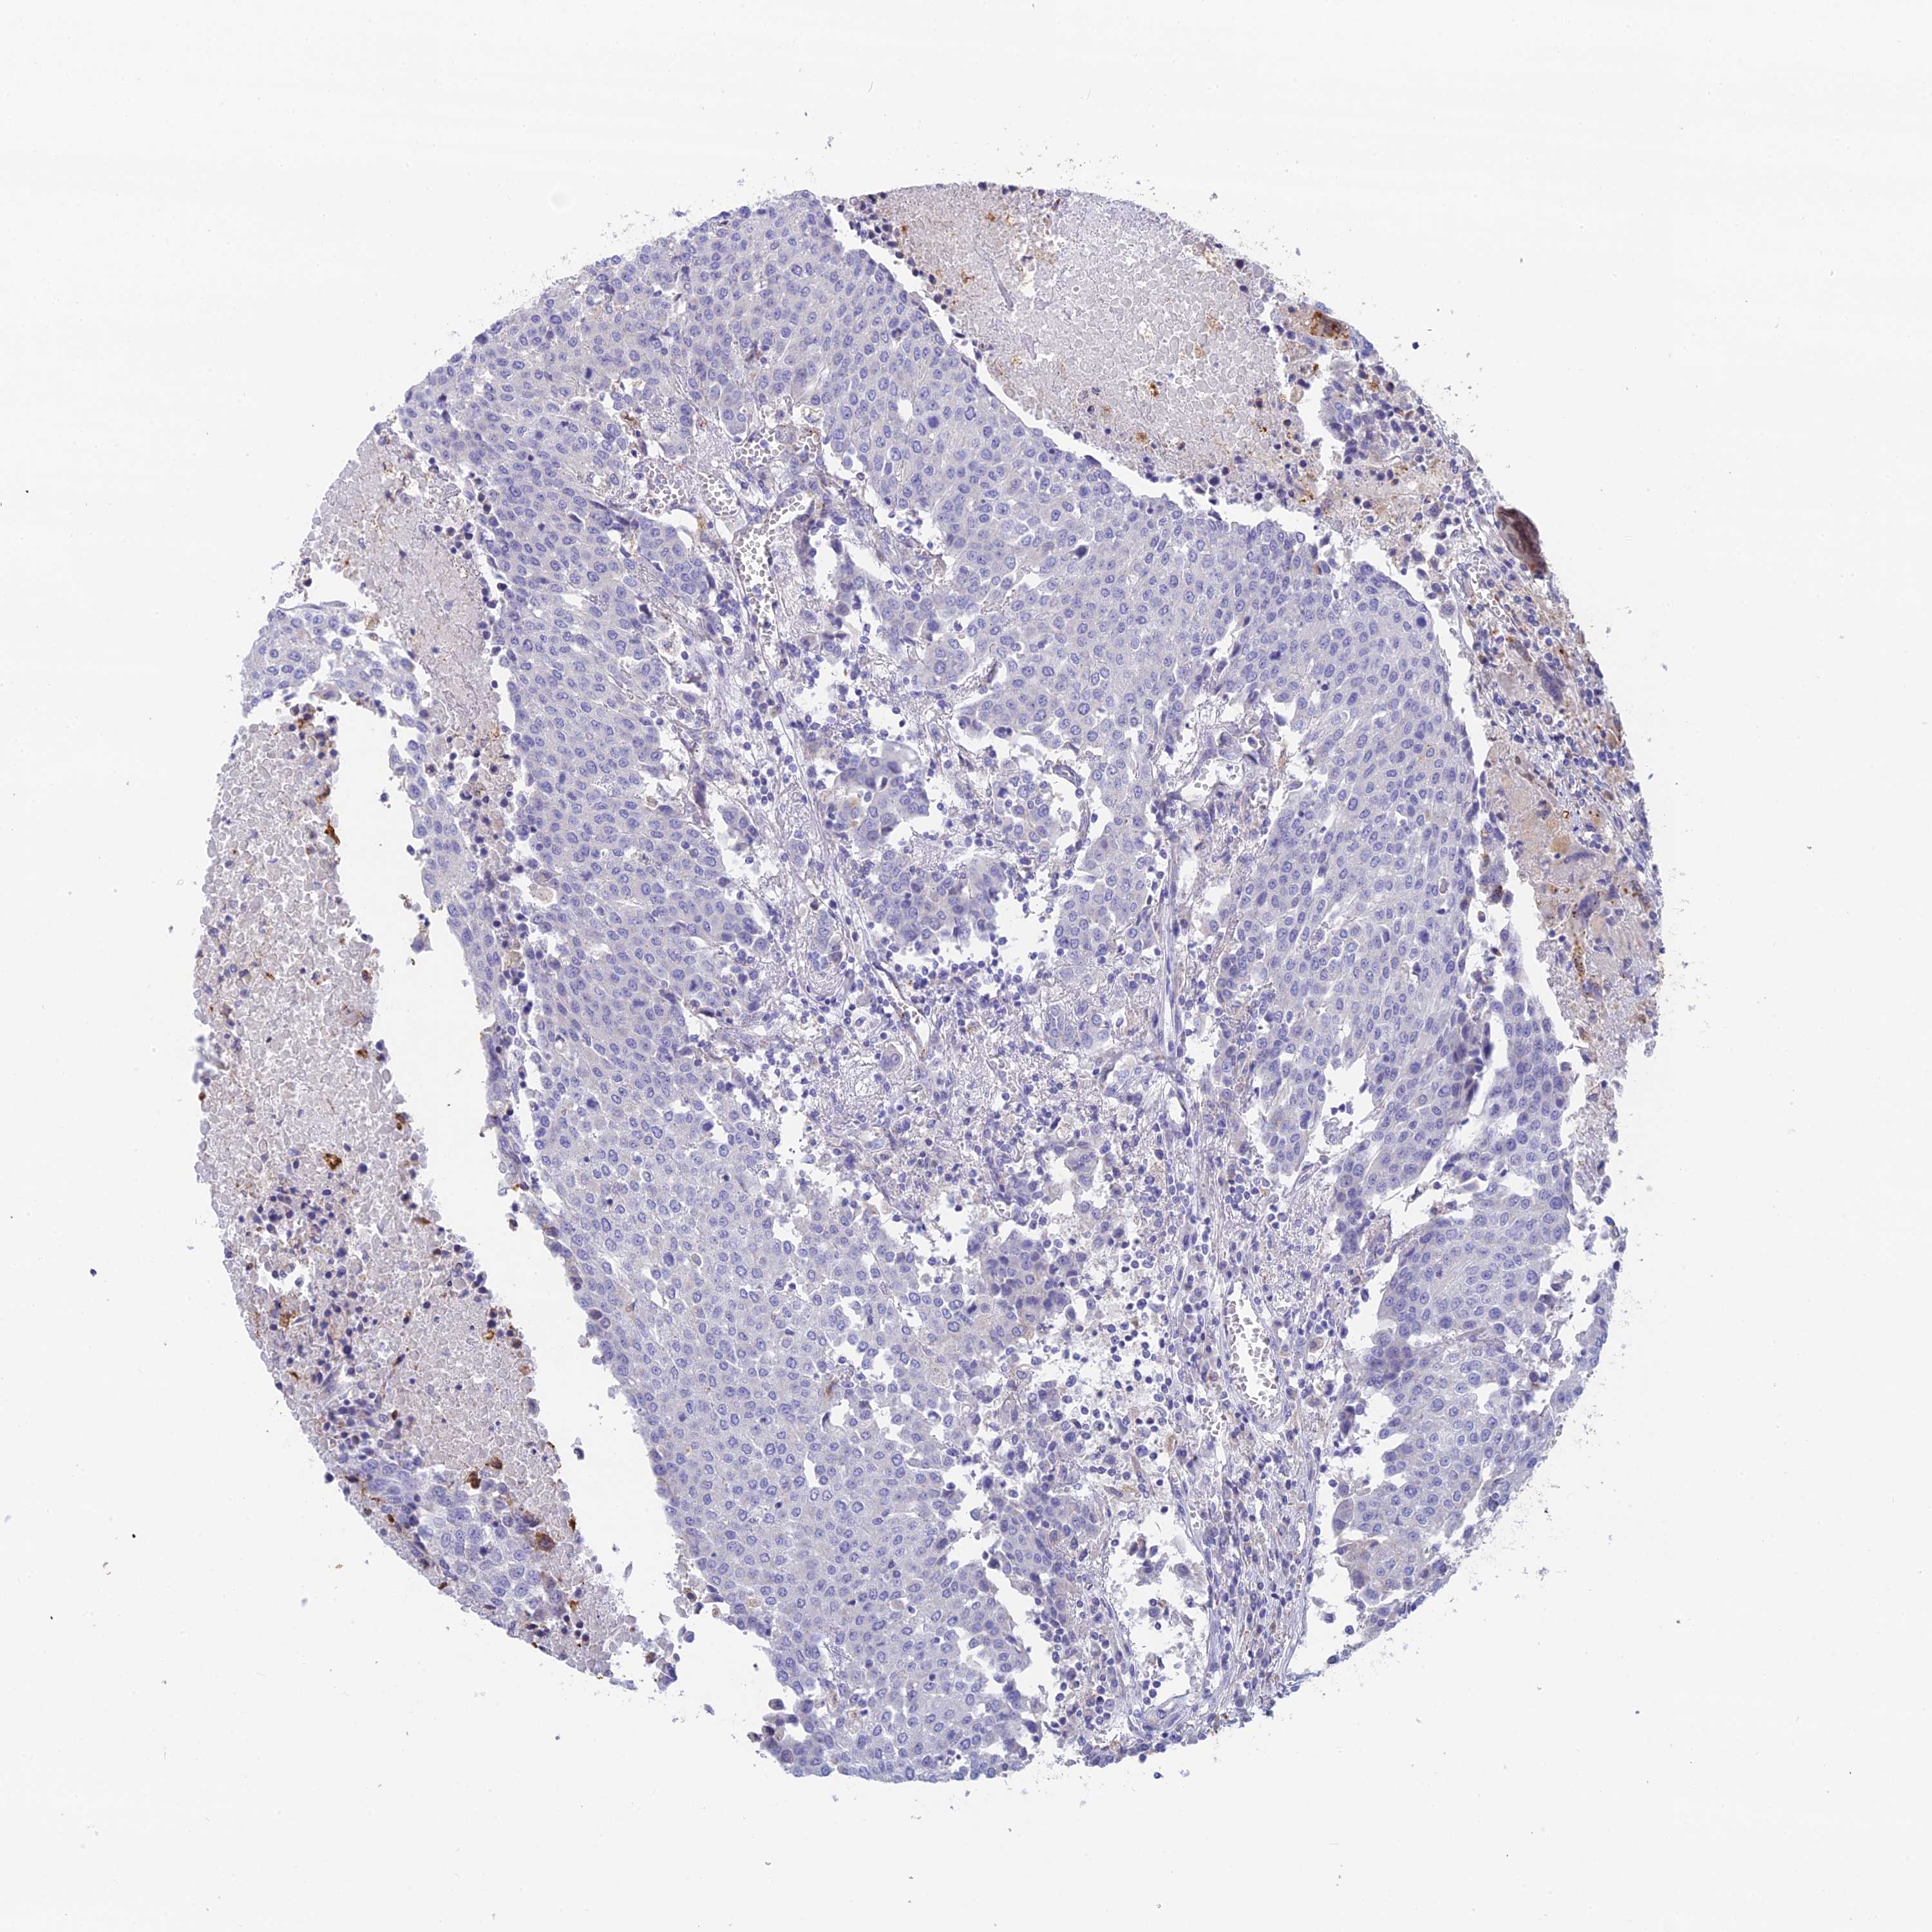

UROTHELIAL CANCER - Protein expressioni

A mouse-over function shows sample information and annotation data. Click on an image to view it in a full screen mode. Samples can be filtered based on level of antibody staining by selecting one or several of the following categories: high, medium, low and not detected. The assay and annotation is described here.

Note that samples used for immunohistochemistry by the Human Protein Atlas do not correspond to samples in the TCGA dataset.

Antibody stainingi

Antibody staining in the annotated cell types in the current human tissue is reported as not detected, low, medium, or high, based on conventional immunohistochemistry profiling in selected tissues. This score is based on the combination of the staining intensity and fraction of stained cells.

Each image is clickable and will lead to virtual microscopy that enables deeper exploration of all samples and also displays staining intensity scores, fraction scores and subcellular localization as well as patient and tissue information for each sample.

Antibody HPA042622

Staining

High

Medium

Low

Not detected

Intensity

Strong

Moderate

Weak

Negative

Quantity

>75%

75%-25%

<25%

None

Location

Nuclear

Cytoplasmic/membranous

Cytoplasmic/membranous,nuclear

Urothelial carcinoma, High grade

Urothelial carcinoma, Low grade